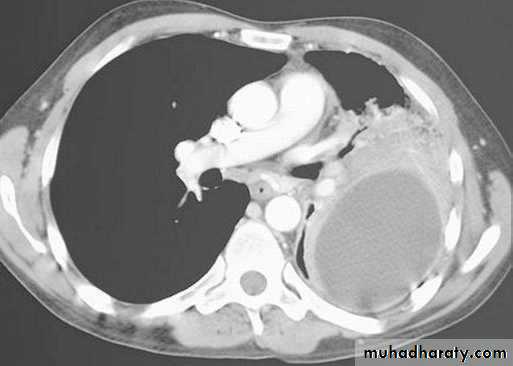

CT

You should be able to diagnose and manage most pneumothoraxes through chest x ray.

Where radiography is not definitive and clinical suspicion is high, a CT scan may be needed.

If you are unable to distinguish between a pneumothorax and large bulla on the basis of the chest x ray, you may need to request a CT scan.

CT adds information regarding the presence or absence of pleural fluid and underlying pulmonary disease.Diseases of the Pleura Dr.Mustafa Nema. Baghdad College of Medicine 2013

emphysematous bulla (not PNX)